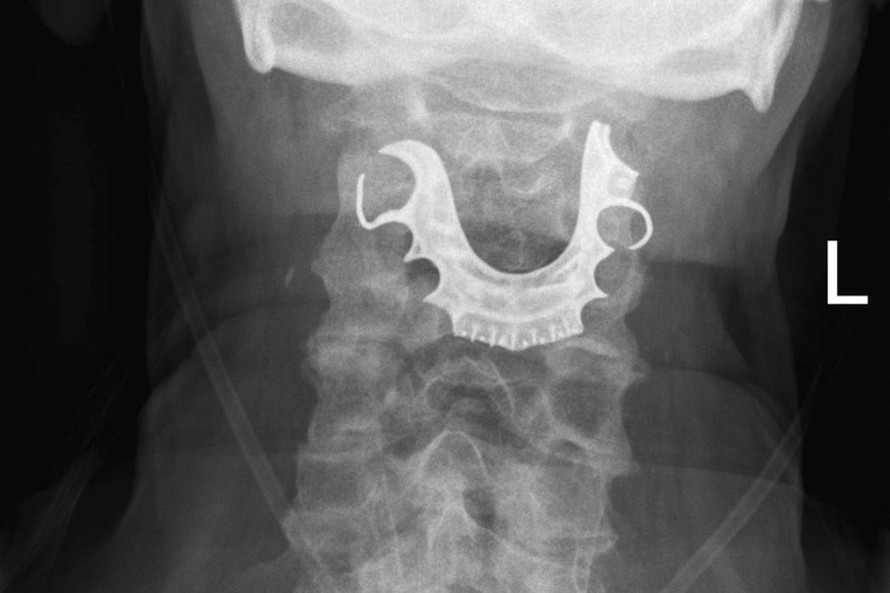

Bệnh nhân đã đi đến phòng cấp cứu sau khi có triệu chứng khó nuốt và bị ho ra máu. Các bác sĩ đã yêu cầu chụp X-quang ngực, chẩn đoán ông bị viêm phổi và điều trị tại nhà bằng kháng sinh cùng steroid. Bệnh nhân phải nhập viện thêm lần nữa và kết quả chụp X-quang khác cho thấy hàm răng giả của người đàn ông này đã mắc kẹt ở đỉnh cổ họng.

Cụ ông cho rằng răng giả của mình bị mất trong khi đang thực hiện một ca tiểu phẫu.

Các bác sĩ không thể kết luận chính xác nguyên nhân khiến hàm răng giả bị tụt xuống cổ họng, nhưng nhiều trường hợp trước đó đã được ghi nhận về việc răng giả bị mất khi bệnh nhân hôn mê trước phẫu thuật.